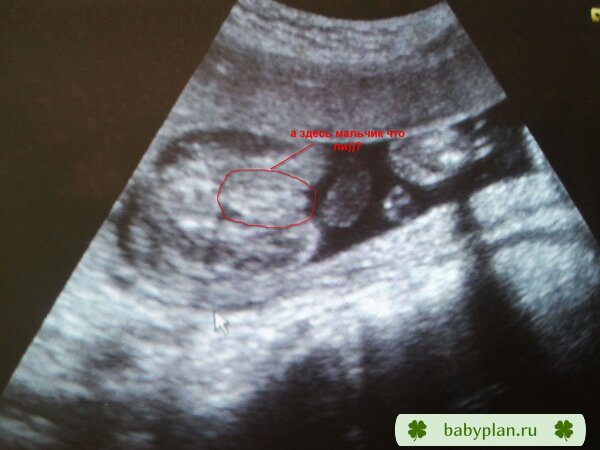

Особенности УЗИ при определении пола ребенка

Раздел: Идеи и советы